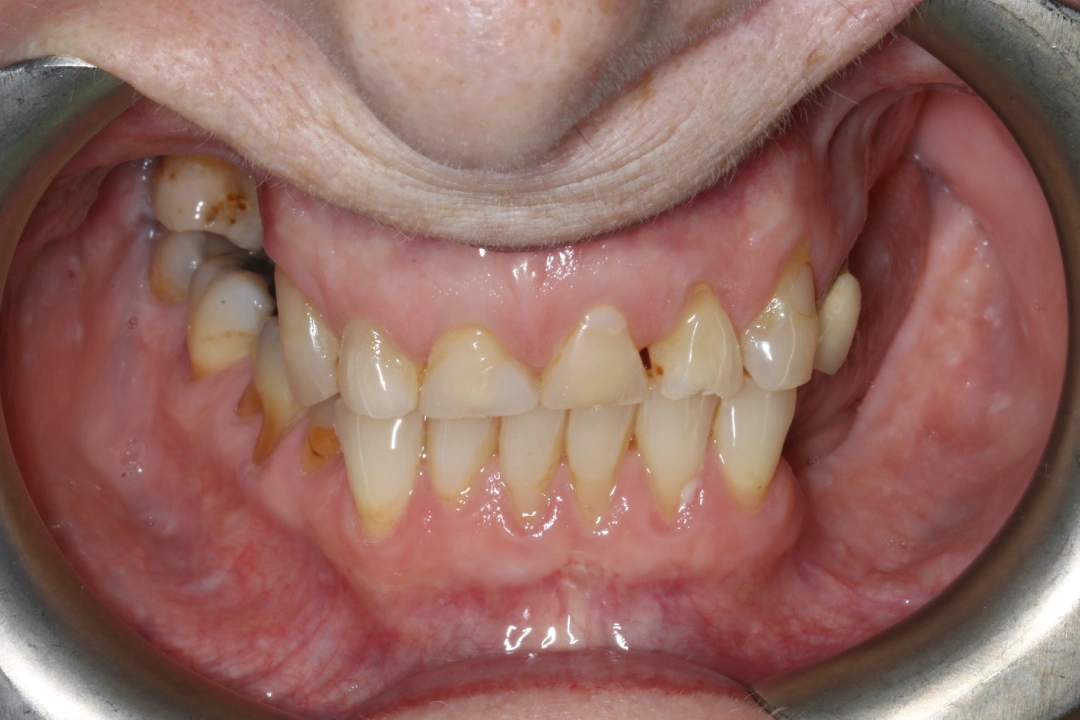

Naomi was unhappy with her worn down, yellow and uneven upper front teeth.

Before